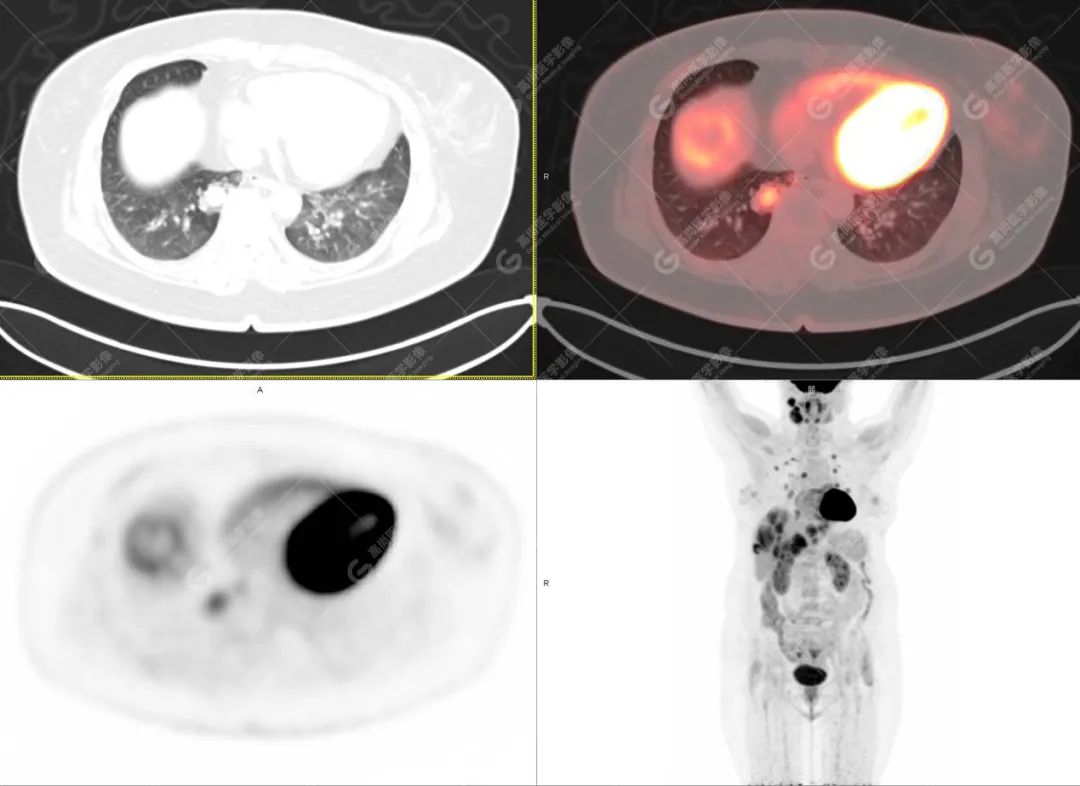

影像诊断:1. 结合病史,右颈部神经鞘瘤(低度恶性)术后改变,右侧颈部稍低密度及等密度结节,代谢异常增高,考虑为肿瘤复发并右颈部淋巴结转移,建议活检。 2. 双侧肺门及纵隔(4R 区)多发肿大淋巴结,代谢异常增高,考虑为转移。 3. 双肺多发大小不等实性结节,部分代谢增高,考虑为转移。 4. 肝脏多发低密度结节及肿块,代谢异常增高,考虑为转移。 5. 右侧第 8 前肋骨骨质破坏,代谢异常增高,考虑为转移。